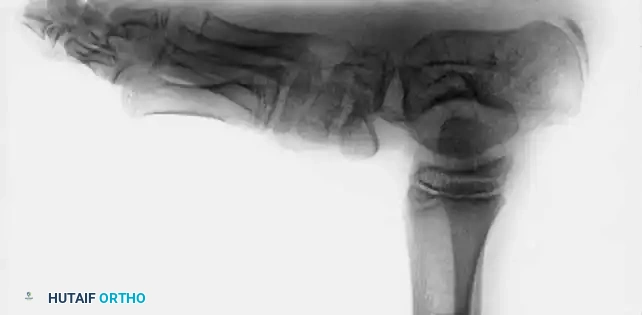

RADIOGRAPHIC EVALUATION

Radiographs are an indispensable adjunct before, during, and after treatment to ensure that clinical correction correlates with true osseous realignment. In the non-ambulatory child, standard imaging includes anteroposterior (AP) and stress dorsiflexion lateral radiographs.

• AP Talocalcaneal Angle (Kite's Angle): Normal is 30 to 55 degrees. In clubfoot, the talus and calcaneus are nearly parallel, progressively decreasing this angle toward 0 degrees as heel varus worsens.

• Lateral Talocalcaneal Angle: Normal is 25 to 50 degrees. In clubfoot, this angle decreases significantly.

• Stress Lateral Tibiocalcaneal Angle: Normal is 10 to 40 degrees. In clubfoot, this angle is often negative, indicating severe calcaneal equinus relative to the tibia.

• Talus–First Metatarsal Angle (AP View): Normal is 5 to 15 degrees. In clubfoot, it is usually negative, reflecting severe forefoot adduction.